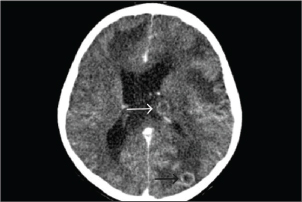

One-week post-VAV-ECMO, while still on corticosteroids for 15 days, the patient developed a new high-grade fever that persisted for 9 days. On day 23 of admission, he complained of progressive headache and agitation. Neurological examination revealed bilaterally dilated (5 mm) but reactive pupils without focal deficits. Emergency contrast-enhanced computed tomography (CT) of the brain demonstrated multiple cerebral abscesses with vasogenic edema and one lesion located at the left periventricular area, adjacent to the lateral ventricle (Fig. 1). In immunocompetent individuals, the most common pathogens were Streptococcus spp., Staphylococcus aureus, Enterobacteriaceae, Pseudomonas aeruginosa, and anaerobes. In immunocompromised hosts, it is most commonly caused by toxoplasmosis, Nocardia spp., Candida spp., Aspergillus spp., and Cryptococcus spp. Empirical antimicrobial therapy was adjusted to intravenous meropenem and vancomycin to provide coverage for multidrug-resistant bacteria and methicillin-resistant Staphylococcus aureus (MRSA). A right frontal craniotomy was subsequently performed for abscess drainage and diagnostic confirmation, along with placement of an external ventricular drain (EVD) in the left lateral ventricle for cerebrospinal fluid (CSF) sampling and intracranial pressure control.

Fig. 1. A computed tomography scan of the brain with contrast on day 23 of admission showed two ring-enhancing lesions located in the left occipital lobe (black arrow) and left periventricular region, adjacent to the lateral ventricle (white arrow).